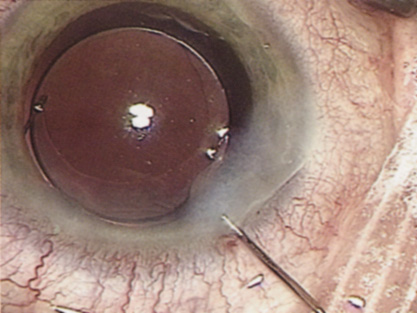

Hydrodissection can be performed after the surgeon has successfully completed capsulorrhexis.97 If the capsulorrhexis is not intact, fluid forced around the interior of the capsule may cause the bag to splay open. With capsulorrhexis, hydrodissection is a safe and extremely useful maneuver. Hydrodissection can be thought of as two maneuvers: hydrodelineation and cortical cleaving hydrodissection. By placing a 27-gauge cannula on a syringe filled with balanced saline solution (BSS), the surgeon can direct fluid beneath the residual anterior capsular rim to create a cleavage plane. Depending on the direction the fluid wave takes, different lamellae of the cataract will be separated. Hydrodelineation is the term used when the cleavage plane separates the adult nucleus from the fetal nucleus or the adult nucleus from the more peripheral epinucleus. Hydrodelineation often results in the characteristic golden ring sign (Fig. 11). Cortical cleavage occurs when the cortex is separated from the capsular bag (Fig. 12). Finding the cortical cleavage plane may be facilitated by gently lifting the capsular margin away from the cortex with the BSS cannula before injecting. Several small bursts of fluid allow the surgeon to monitor progress of the fluid wave. When dealing with a soft nucleus, the authors strive to perform true cortical cleaving hydrodissection. For a hard nucleus, hydrodelineation allows manipulation of less of the nuclear bulk, although the remaining epinuclear shell must be addressed in an additional step. Hydrodelineation is particularly useful if the nucleus is not freely mobile after cortical cleaving hydrodissection.

Fig. 12. Hydrodissection, performed subincisionally with a 27-gauge J-cannula, produces a cleavage plane between the capsule and the cortex. The small blue arrows indicate the advancing fluid wave.